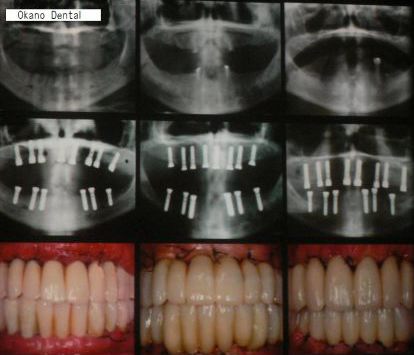

| A手術当日に仮歯のブリッジが入るオールオン6 (ノーベルバイオケア使用症例) |

| この症例の場合は、顎の骨の幅は、あまり広くはなかったですが 上顎洞までの距離があって13mmの長さのインプラントを選択することができたので 6本のインプラント(条件が整えばノーベルバイケアインプラント推奨)で行いました。 |

| これは、インプラントを入れた当日に仮の歯をブリッジにしていれた状態のレントゲンです。 インプラントを埋入するときのトルクが35N(ニュートン)から40Nの範囲で埋めることができないと その場で仮歯を入れて咬めるようにして帰っていただくこと(即時荷重)が出来ません。 骨がある程度硬くないと無理ですし、また、軟らかい骨でも削るのではなく押し広げるように形成することによって このトルクを作るようにします。 最初のドリルの感じで、どのように押し広げれば 適正なトルクで埋入することが出来るかがイメージ出来なければ無理です。 また、骨の幅がギリギリでシミュレーションとの誤差が0.3mm以内の精度でしかも方向を合わせなければいけません。 文字通り職人技です。 これが出来る歯科医師は、兵庫県でも極少数だと自負しております。 |

先の症例@の方と同じく、笑気麻酔などを使用しました。 総入れ歯と、このようになるのとでは咬めることはもちろん、気分が違ってきて若返られています。 |

| 上顎の症例ばかりですが、一般的に下顎は上顎に比べて骨が硬くインプラントが埋めやすいです。 特に、困難と思われる上顎の一気に全てを埋入する症例を出しました。 |